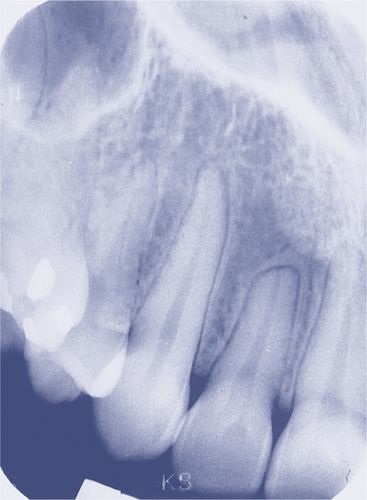

Which of the following statements BEST describes the anomaly in the image shown below?

E. External resorption of the root